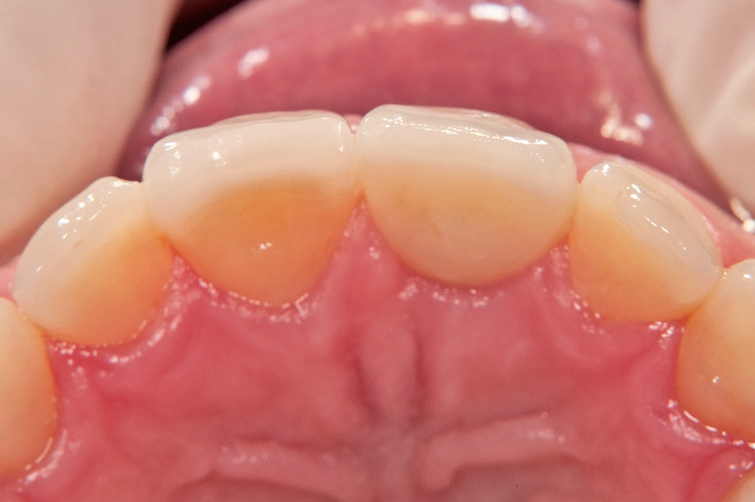

Gleichzeitig mit der prothetischen Versorgung des Implantats wurde auch für Zahn 11 ein Veneer geplant. Zum Einsatz kam ein Zeramex T Implantat Durchmesser 5,5 mm, Länge 12 mm. Für die Kronenversorgung wurde ein mit e. Max überpresstes CAD-Abutment gewählt. Während der Einheilphase des Implantats kam eine Sunflex-Prothese zum Einsatz.